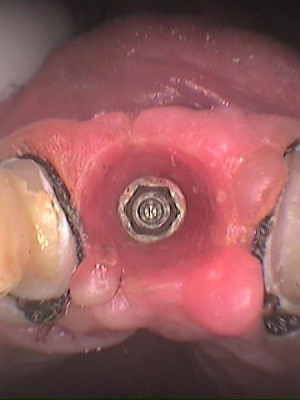

Vista oclusal previa impresión

Se remueve tornillo de cicatrización